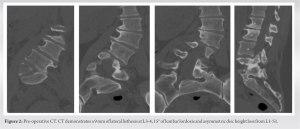

Pre-operative planning was performed through the Aprevo software (Carlsmed, Carlsbad, CA) and a 3D reconstruction was performed. Customized 3D printed titanium implants were computationally constructed using pre-operative CT images (Fig. 3 and 4).

The patient underwent a staged procedure. In Stage 1 (Fig. 5), the patient underwent an L4-S1 posterior column osteotomy in the prone position to mobilize the L4-S1 segment, following which a L3-4 and L-S1 ALIF was performed. Stage 2 of the surgery was performed 2 days later, in which a lateral lumbar interbody fusion using the customized interbodies was performed at L1-2 and L2-3 followed by posterior spinal fusion at T10-Pelvis. The patient had an uncomplicated hospital stay and discharged to a short-term rehabilitation facility.

The objectives of this study were to (1) illustrate an example of successful surgical treatment of a patient with hemivertebrae using custom patient-specific implants at multiple spinal levels and (2) compare this case a to a similar case that utilized standard implants. The patient in Case 1 suffered from chronic low back pain due to CS and a right wedge vertebra. Following lumbar decompression and fusion using customized 3D-printed implants, the patient reported significant improvement in her pain and posture (Fig. 6). Given the anatomic complexity of these patients, the development and utilization of customized implants allowed for an excellent endplate apposition without the need for extensive bony resection, which would not be possible with standard interbodies. To our knowledge, this is the first reported case demonstrating the treatment of CS using 3D-printed personalized spinal implants for multiple spinal levels. Studies evaluating the efficacy of personalized spinal implants are largely limited to case studies. Two of these studies reported the use of these implants in the treatment of congenital spinal disorders. Mobbs et al. [14] presented a 52-year-old woman with an 18-month history of back pain. Similar to our patient, their patient was found to have a congenital hemivertebra at L5 (Fig. 1 and 2) with degenerative changes that was treated with lumbar decompression and fusion with a personalized spinal implant. However, while only the L4/L5 segment was fused in Mobbs et al. case, the patient in our case underwent L3-S1 ALIF and posterior instrumentation T10-Pelvis (Fig. 4 and 5), demonstrating increased severity and unique complexity in our case. In another study [15], a 34-year-old man presented with a 3-year history of bilateral L5 radiculopathy caused by bilateral L5 pars defect, L5/S1 degenerative disc disease, and severe foraminal stenosis. Anterior lumbar interbody fusion surgery was performed with custom 3D interbodies. Again, our case differed from this case in complexity of procedure and medical history as we performed a multilevel deformity surgery using multilevel customized implants. To address our second objective, we compared Case 1 to Case 2, where the patient underwent an index lumbar decompression and fusion for CS (Fig. 7 and 8) using standard titanium implants. At 2-year post-operative, the patient in Case 2 presented with worsening sacroiliac pain with the evidence of rod fracture and pseudoarthrosis at L4-L5 (Fig. 9). Revision surgery resulted in improved pain and mobility (Fig. 10). Development of pseudoarthrosis and the need for revision surgery in Case 2 may be explained by the decreased surface area available for fusion, decreased contact of the implant with the bone, thus decreased on-growth and through-growth resulting in decreased osteointegration, and stability as compared to Case 1, which utilized custom implants. While larger, randomized, controlled studies are still needed to gain knowledge pertaining to long-term outcomes in comparison to traditional, non-customized implants, existing biomechanical and animal investigations of customized implants suggest they will provide improved outcomes and increased surgical safety and efficiency. In a study evaluating the biomechanical properties of titanium cages in cervical spine surgery, Fengbin et al. found that implants with increased end plate contact surface area resulted in decreased loss of height of fused segments, lower rate of subsidence, and lower scores of neck pain [16]. During an en bloc resection of L5 vertebral body with single lesion, Mobbs et al. compared reconstruction using a 3D patient-specific implant and an off-the-shelf implant at the same spinal level intraoperatively. The 3D patient-specific implant resulted in decreased time to implant, reduced radiographs required to determine the position of implant, improved end plate fit, and more uniform loading compared to the off-the-shelf implant [5]. From a safety perspective, 3D-implants seem to provide benefit over off-the-shelf implants as they avoid osteotomies required with off-the-shelf implants, thus decreasing operative time and blood loss, as well as allow for pre-planned screw trajectories which decrease the chance of damage to blood vessels, nerves, and the spinal cord [17]. The utility of 3D customized implants in allowing surgeons to operate on native anatomy will be safer, quicker, and result in increased osteointegration and bone/implant interface.